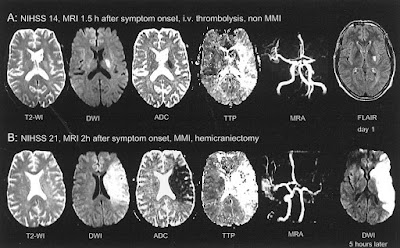

Τα συμπιεστικά φαινόμενα με επακόλουθη αύξηση της ενδοκράνιας πίεσης αποτελούν μια άλλη μορφή δευτεροπαθούς εγκεφαλικής βλάβης που μπορεί να οδηγήσει σε επιδείνωση της εγκεφαλικής ροής αίματος. Μια μορφή ισχαιμικού ΑΕΕ, που είναι γνωστό ότι προκαλεί οίδημα και σημαντικά συμπιεστικά φαινόμενα είναι αυτή που ονομάζεται «κακόηθες εγκεφαλικό έμφρακτο» [malignant cerebral infarction]. Αυτο τυπικά εμφανίζεται σε συνθήκες απόφραξης της έσω καρωτίδας ή της μέσης εγκεφαλικής αρτηρίας. Σε τέτοιες περιπτώσεις, μπορεί να εμφανιστεί μαζικό εγκεφαλικό οίδημα, που προκαλεί εγκολεασμό και επακόλουθο εγκεφαλικό θάνατο.

Για τους ασθενείς με υποψία αυξημένης ενδοκράνιας πίεσης, η τοποθέτηση συσκευής συνεχούς καταγραφής της ενδοκράνιας πίεσης ή η κοιλιοστομία είναι απαραίτητες για την επιθετική αντιμετώπιση. Κάποιο ωσμωτικά δρον φάρμακο, όπως είναι η μαννιτόλη ή ο υπέρτονος φυσιολογικός ορός, μπορεί να χορηγηθεί για τη μείωση της ενδοκράνιας πίεσης, αλλά αυτό συχνά είναι ένα μέτρο που απλώς κερδίζει χρόνο. Για ασθενείς με συμπτωματικά συμπιεστικά φαινόμενα, θα πρέπει να λογαριάζεται και η ημικρανιεκτομή. Η φαρμακευτική και χειρουργική αντιμετώπιση του κακοήθους εγκεφαλικού οιδήματος και ο ρόλος της ημικρανιεκτομής στο οξύ εγκεφαλικό έμφρακτο δεν ανήκουν στο σκοπό αυτής της ανασκόπησης. Ωστόσο, είναι σημαντικό να θυμάται κάνεις ότι για την πρόληψη της περαιτέρω ισχαιμίας, θα πρέπει κανείς να διατηρήσει επαρκή εγκεφαλική αιμάτωση. Η πίεση εγκεφαλικής αιμάτωσης μπορεί να υπολογιστεί εάν είναι διαθέσιμες οι τιμές της ICP και της MAP μέσω της συνεχούς καταγραφής, μέσω της εξίσωσης CPP = MAP – ICP. Για τους περισσότερους ασθενείς με ισχαιμικό ΑΕΕ, η CPP θα πρέπει να διατηρείται στο εύρος των 65 έως 70 mm Hg ή υψηλότερα. Οι τιμές της πίεσης εγκεφαλικής αιμάτωσης που υπερβαίνουν τα 130 mm Hg μπορεί να οδηγήσουν σε υπεραιμία, επιδείνωση του εγκεφαλικού οιδήματος ή αιμορραγία.